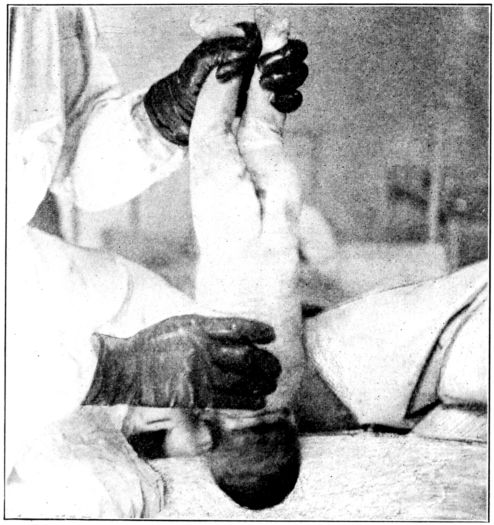

| 157. | Cord dressed with dry sterile gauze | 470 |

| 158. | Abdominal binder applied over cord dressing | 471 |